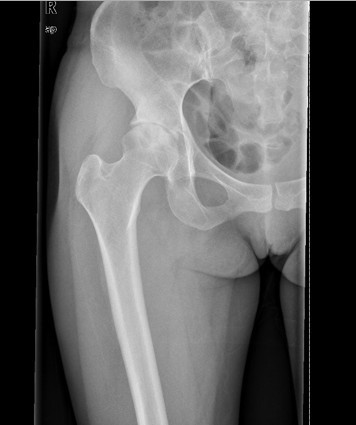

查体:右髋部软组织未见肿胀,双下肢皮肤无破溃,双足趾间皮肤干燥、完好。右髋部后侧轻压痛,双侧足背动脉和胫后动脉搏动正常。 辅查:X线:双侧侧髋臼较浅,髋臼外上方软骨下骨硬化及骨赘,Sharp角右侧约48°、左侧约50°,CE角右侧约20°、左侧约18°,右侧髋关节间隙狭窄,右侧髋臼、股骨头可见囊性改变。

诊断: 1.右侧髋关节发育不良骨关节炎(crowe I型) 2.左侧髋关节发育不良(crowe I型) 3.上呼吸道感染 治疗:排除手术禁忌症后择期手术治疗。